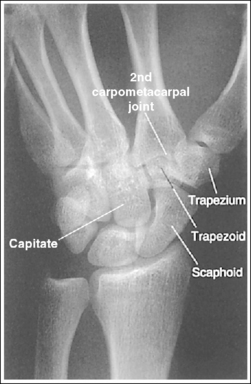

See Figure 4-34 and Box 4-12.

The wrist has been externally rotated to a 45-degree PA oblique projection. The trapezoid and trapezium are demonstrated without superimposition, and the trapeziotrapezoidal joint space is open. The scaphoid tuberosity and waist are demonstrated in profile. Only a small degree of trapezoid and capitate superimposition is present.

• To accomplish a PA oblique wrist projection, begin with the wrist in a PA projection, with the humerus and the forearm on the same horizontal plane. Externally rotate the hand and wrist until the wrist forms a 45-degree angle with the IR (Figure 4-35). When judging the degree of wrist obliquity, it is best to view the wrist and not the hand. The obliquity of the hand and wrist are not always equal when they are rotated, especially if the humerus and forearm are not positioned on the same horizontal plane for the image.

• Determining the accuracy of wrist obliquity. On a PA wrist projection (see Image 39), the trapezoid and trapezium are superimposed. Placing the wrist in a 45-degree externally rotated PA oblique projection draws the trapezium from beneath the trapezoid, providing clear visualization of both carpal bones and the joint space (trapeziotrapezoidal) between them. The PA oblique projection also rotates the scaphoid tuberosity and waist into profile. The relationships between the trapezoid and trapezium and the trapezoid and capitate are used to discern an accurate PA oblique wrist projection. If the wrist is underrotated, the trapezoid and trapezium are superimposed, the trapeziotrapezoidal joint space is obscured, and the trapezoid demonstrates minimal capitate superimposition (see Image 40). If wrist obliquity is more than 45 degrees, the trapezium demonstrates minimal trapezoidal superimposition, the capitate is superimposed by the trapezoid, and the trapeziotrapezoidal joint space is obscured (see Image 41).

The second CM and the scaphotrapezoidal joint spaces are demonstrated.

• For the PA wrist projection, the CM joints are opened by flexing the hand until the metacarpals are at a 10- to 15-degree angle to the IR. When the hand and wrist are placed in obliquity, the same metacarpal tilt must be maintained to open the second CM and scaphotrapezoidal joint spaces. If the distal second metacarpal is positioned too far away from the IR, a portion of the metacarpal (MC) superimposes the trapezoid, closing the second CM and scaphotrapezoidal joints (see Image 40).

The long axes of the third metacarpal and midforearm are aligned with the long axis of the collimated field. The scaphoid tuberosity and waist are demonstrated in profile and are not positioned directly next to the radius.

• If the long axes of the third metacarpal and midforearm are aligned with the long axis of the collimation field, the patient's wrist is placed in a neutral position. Radial deviation increases the foreshortening of the scaphoid, preventing visualization of the scaphoid tuberosity and waist, and positions the scaphoid directly next to the radius (see Image 42). Ulnar deviation decreases scaphoid foreshortening (see Image 43).

The carpal bones are at the center of the exposure field. The carpal bones, one fourth of the distal ulna and radius, and half of the proximal metacarpals are included within the collimated field.

• The wrist joint is located at the base of the first proximal metacarpal. To obtain a PA oblique projection of the carpal bones with the least amount of distortion, place a perpendicular central ray at this level and centered with the midwrist area. Open longitudinal collimation to include half of the metacarpals. Transversely collimate to within 0.5 inch (1.25 cm) of the wrist skin line.